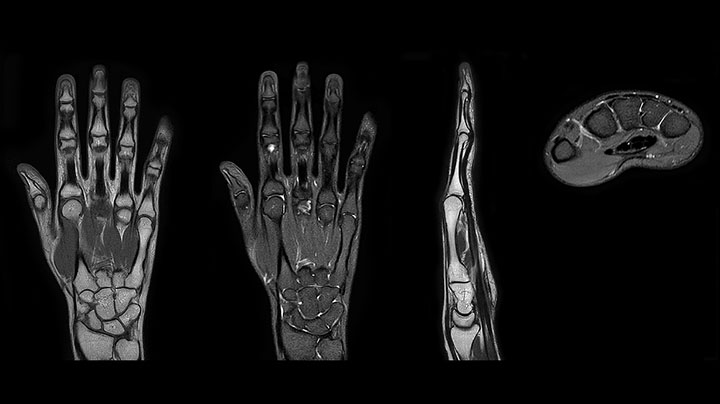

Prodiva imaging of the hand covers the fingertips and includes the full wrist as well. The dS MSK M coil is easy to use.

Scan time 2:55 min, FOV 160 mm, acq voxels 0.55 x 0.83 x 3.0 mm.

Scan time 4:19 min, FOV 160 mm, acq voxels 0.55 x 0.80 x 3.0 mm.

Scan time 2:50 min, FOV 160 mm, acq voxels 0.70 x 0.99 x 3.0 mm.